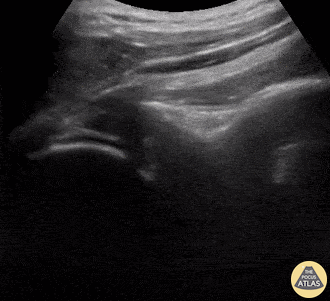

A 9-year-old female presented with left shoulder pain. She has a history of multiple dislocations and, as seen here on POCUS, is able to reduce the dislocation herself. Julie Klensch, PEM Fellow & Paul Khalil, MD University of Louisville/Norton Children's Hospital